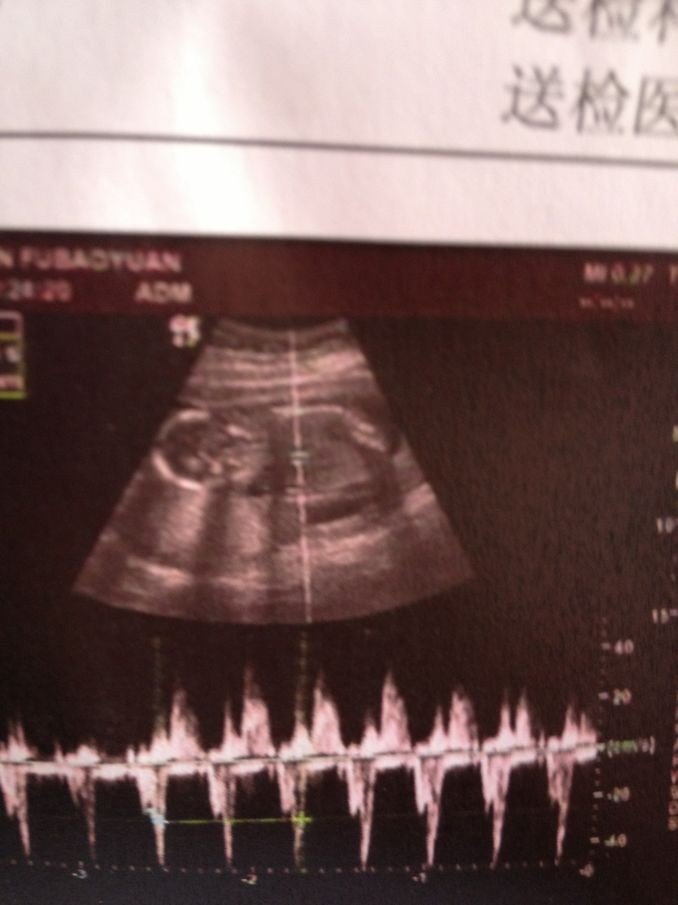

大家能不能帮我看一下我的B超图宝宝是男孩女孩

亲抹挤婚这张图谁都不敢确定 除非医生在帮你照的时候鉴定 男孩女抗室孩都愚卫是咱家宝贝

B超是看不出来的,四维能看的出来,但是现在的医生不会告诉你的,反正都是自己的,男女也没那么重要吧

这怎么看得出来,看样子就二十多周。